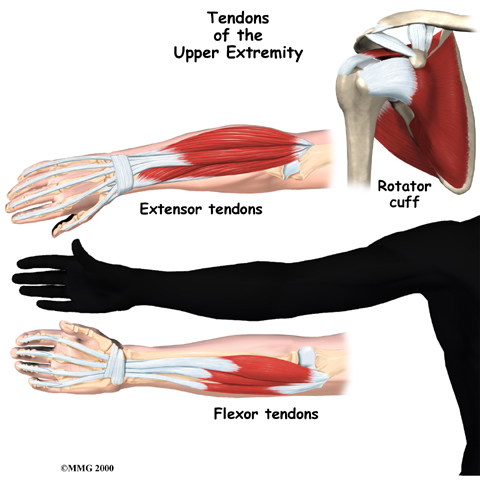

Many parts of the tendon can be injured. Tendon problems can involve the area where the tendon attaches to the bone, the tissue that surrounds the tendon (the tendon sheath), or the main tissues of the tendon. Doctors use different terms to refer to injuries of different parts of the tendon.

Tendon injuries can show up anywhere in your body. Doctors see tendonitis most often in certain sites.

De Quervain's Disease and Trigger Finger

Tendon problems are common in the hand and wrist. De Quervain's disease causes pain in the wrist just above the thumb.

Trigger finger generally causes pain in the palm just below the knuckles, but it eventually causes problems with movement.

Lateral Epicondylitis

Lateral epicondylitis, also called:

Tennis Elbow

affects the area where the tendons of the elbow attach to bone on the outside of the elbow. It causes pain when using the wrist and hand.

affects the area where the tendons of the elbow attach to bone on the outside of the elbow. It causes pain when using the wrist and hand.

Medial Epicondylitis

Medial epicondylitis, also called:

Golfer's Elbow

affects the area where the tendons of the elbow attach to bone on the inside of the elbow. It causes pain when using the wrist and hand.

Rotator Cuff Tendonitis

Rotator cuff problems of the shoulder range from mild damage to:

Complete Tears

They can cause pain even when resting.

Related Document: FYZICAL Naples (Pelican Bay)'s Guide to Rotator Cuff Disease